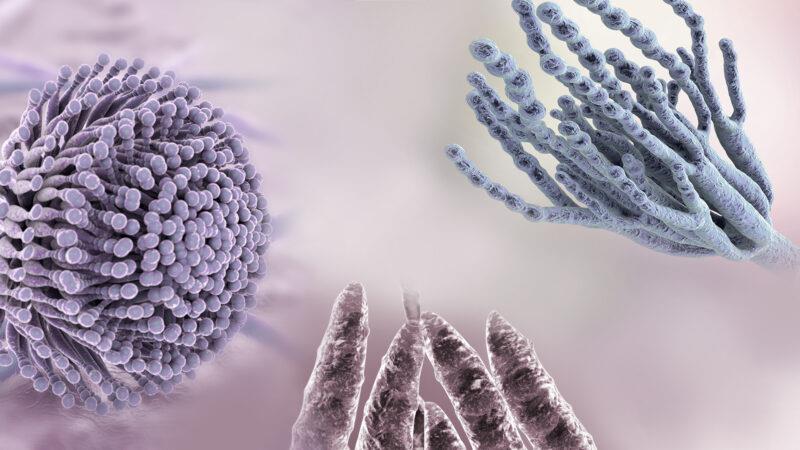

قیمت: 22٬000 تومان - دسته بندی فایل: علوم پزشکیپاورپوینت مایکوتوکسین ها

فروش ویژه پاور پوینت حرفه ای مایکوتوکسین ها با تخفیف استثنایی فقط 49 هزار تومان تعداد اسلاید: 15 اسلاید